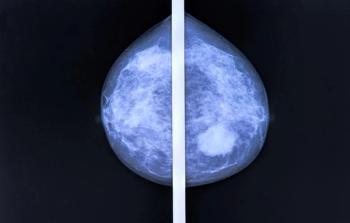

Updates from the ongoing INSEMA trial suggest that patients with early-stage breast cancer maintain superior quality of life by forgoing sentinel lymph node biopsy and axillary lymph node dissection.